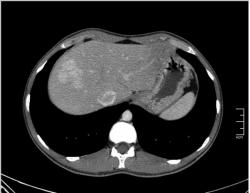

КТ печени. Наблюдения для размышления.

Уважаемые коллеги, особенно врачи КТ. Надеюсь что данная публикация окажется полезной для многих из Вас. Ниже представлены сканы печени; предлагаю Вам ознакомится с ними и высказать свое мнение. Пациент мужчина средних лет, специфичных жалоб не предъявляет.

Нет, Вы не правы. Во первых нельзя адекватно судить о состоянии стенок желудка при отсутствии его контрастирования. В желудке гиподенсивное содержимое (жидкость), стенки спавшиеся, видны складки. Я написал в оглавлении, что публикую КТ именно ПЕЧЕНИ.

Если Вы не против, я немного придержу продолжение данного наблюдения. Основная задача данной публикации не сам диагноз, а показать современные аспекты и особенности метода КТ, а также важность глубины и объёма знаний врачей радиологов которые занимаются КТ диагностикой.

Ну, мне не нравится один маленький гиподенсный очажок в 8 сегменте.

И как его можно трактовать?

На гемангиому похоже, контрастировать бы надо.

P.S. не судите строго, КТ не занимаюсь

Евгений: В принципе похоже, весьма может быть. Тогда это простая инциденталома, т.е. находка не имеющая значения. А КТ с контрастом, обратите внимнаие на контрастированные гиперденсные печёночные вены.

Nela: Браво! Есть непрямые (вторичные) признаки объёмного образования печени (анатомия, анатомия и ещё раз анатомия. )

Вариант, но в принципе по КТ можно разрешить до 95% всех вопросов связанных с образованиями печени. По большому счёту, только цирроз печени с узлами регенерации и с подозрением на наличие гепато-целлюлярной карциномой является абсолютным показанием к таргетной МРТ печени; ну и МР-холангиография, когда невозможно выполнить ЭРХПГ.

А может в отсроченной венозной фазе всё ясно станет, если образование есть, оно накопит какое то количество контраста.

Уважаемый v1tal! Огромная Вам благодарность; Вы назвали ключевое слово: фаза! Высказанная Вами мысль, это моя основная цель данной публикации. Постараюсь позже более детально объяснить почему. Представленные сканы выше, были выполнены на стандартной портальное фазе. А сейчас, я покажу сканы данного пациента выполненные на артериальной фазе :

Это может быть нодуллярной гиперплазией? Еще бы рубец законтрастировался в отсроченную фазу.

Доктор Марио! С объемным образованием печени все понятно. У меня вопрос. Почему сразу стали выполнять КТ печени, а не УЗИ? Или пациенту было выполнено УЗИ и потом КТ.

Да Ola la, Вы абсолютно правы; это Фокальная Нодулярная Гиперплазия печени (FNH Focal Nodular Hyperplasia). Одна из немногих гиперваскулярных опухолей печени. Наверное некоторые коллеги спросят, и зачем было изначально публиковать портальную фазу, на которой «не видно» (хотя опухоль видна, пусть и не напрямую, и Nela это доказала); и только потом показывать сканы на артериальной фазе, на которой всё «красиво и показательно». Постараюсь объяснить.

За эти два года, в течении которых я познакомился с радиологическим русскоговорящим интернетом, я пришёл к определённым выводам. К сожалению, при наличии уже довольно неплохого парка современной аппаратуры в клиниках России и СНГ (у меня лично аппаратура намного скромнее по возможностям чем например у Nela или v1tal), ощущается огромный пробел в знаниях очень многих врачей, которые работают на этих аппаратах. И как следствие, врачи классические рентгенологи, отправляя пациентов на до-обследование в эти клиники, получая при этом неудовлетворительный результат проведённых исследований, начинают полагать (и имеют на это право), что зачем все эти «КТ и МРТ», если мы по своим стандартным рентгенологическим методикам получаем тот же результат (если иногда и не лучше-живой пример тому публикация vital с дивертикулом пищевода, где врач КТ написал диафрагмальную грыжу). И когда я читаю такие посты, мне становится очень обидно, хотя повторюсь, я уже пониманию причины такого мышления. Тем более что мало кто знает, что КТ и МРТ это не «статические методики», при которых взял пациента, положил на стол, дал контраст (как, куда, на какой скорости-мало кого волнует), сделал одну спираль/фазу, и до свиданья, «подавайте» следующего. Современные протоколы КТ и МРТ выработаны ПОД КАЖДЫЙ КОНКРЕТНЫЙ ДИАГНОЗ, иными словами, если мы подозреваем заболевание кишечника, и снимем пациента по протоколу разработанному для диагностики патологии печени или поджелудочной, то мы можем пропустить «всё на свете» в кишечнике, и при этом ничего не найти в печени или панкреас.